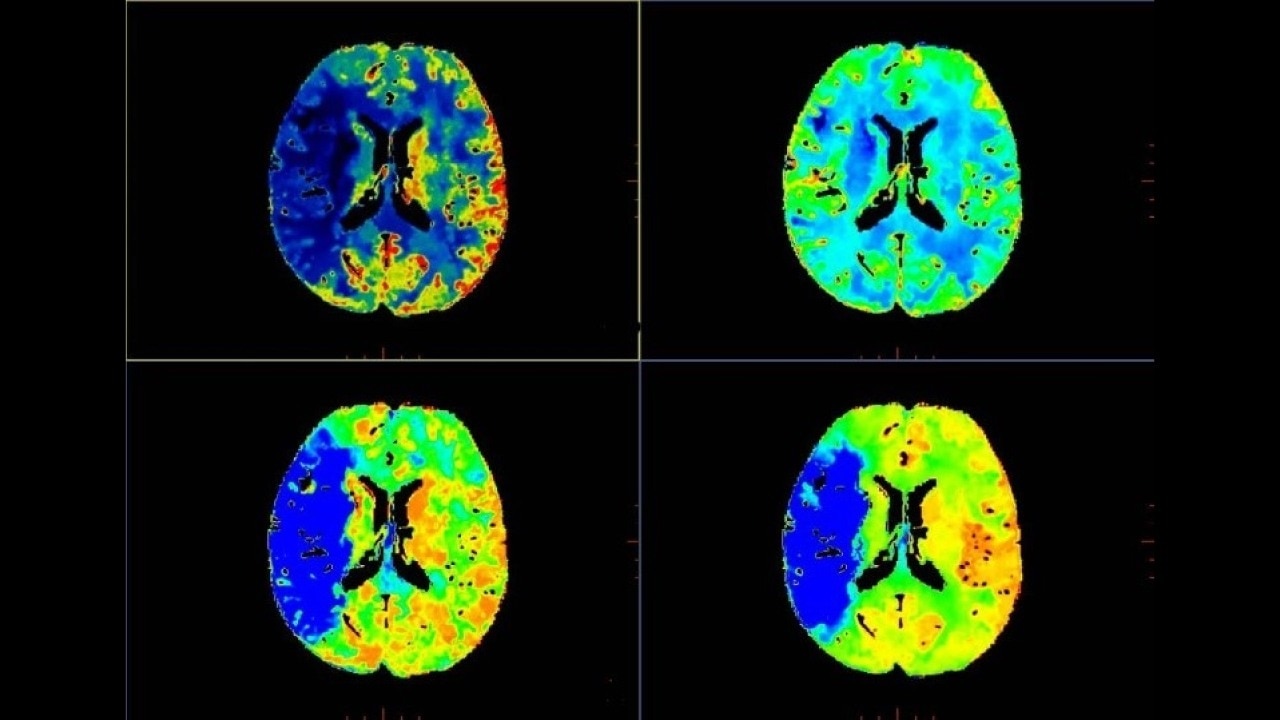

Brain perfusion

Easy-to-use automated workflow for CT stroke and tumor angiogenesis evaluation